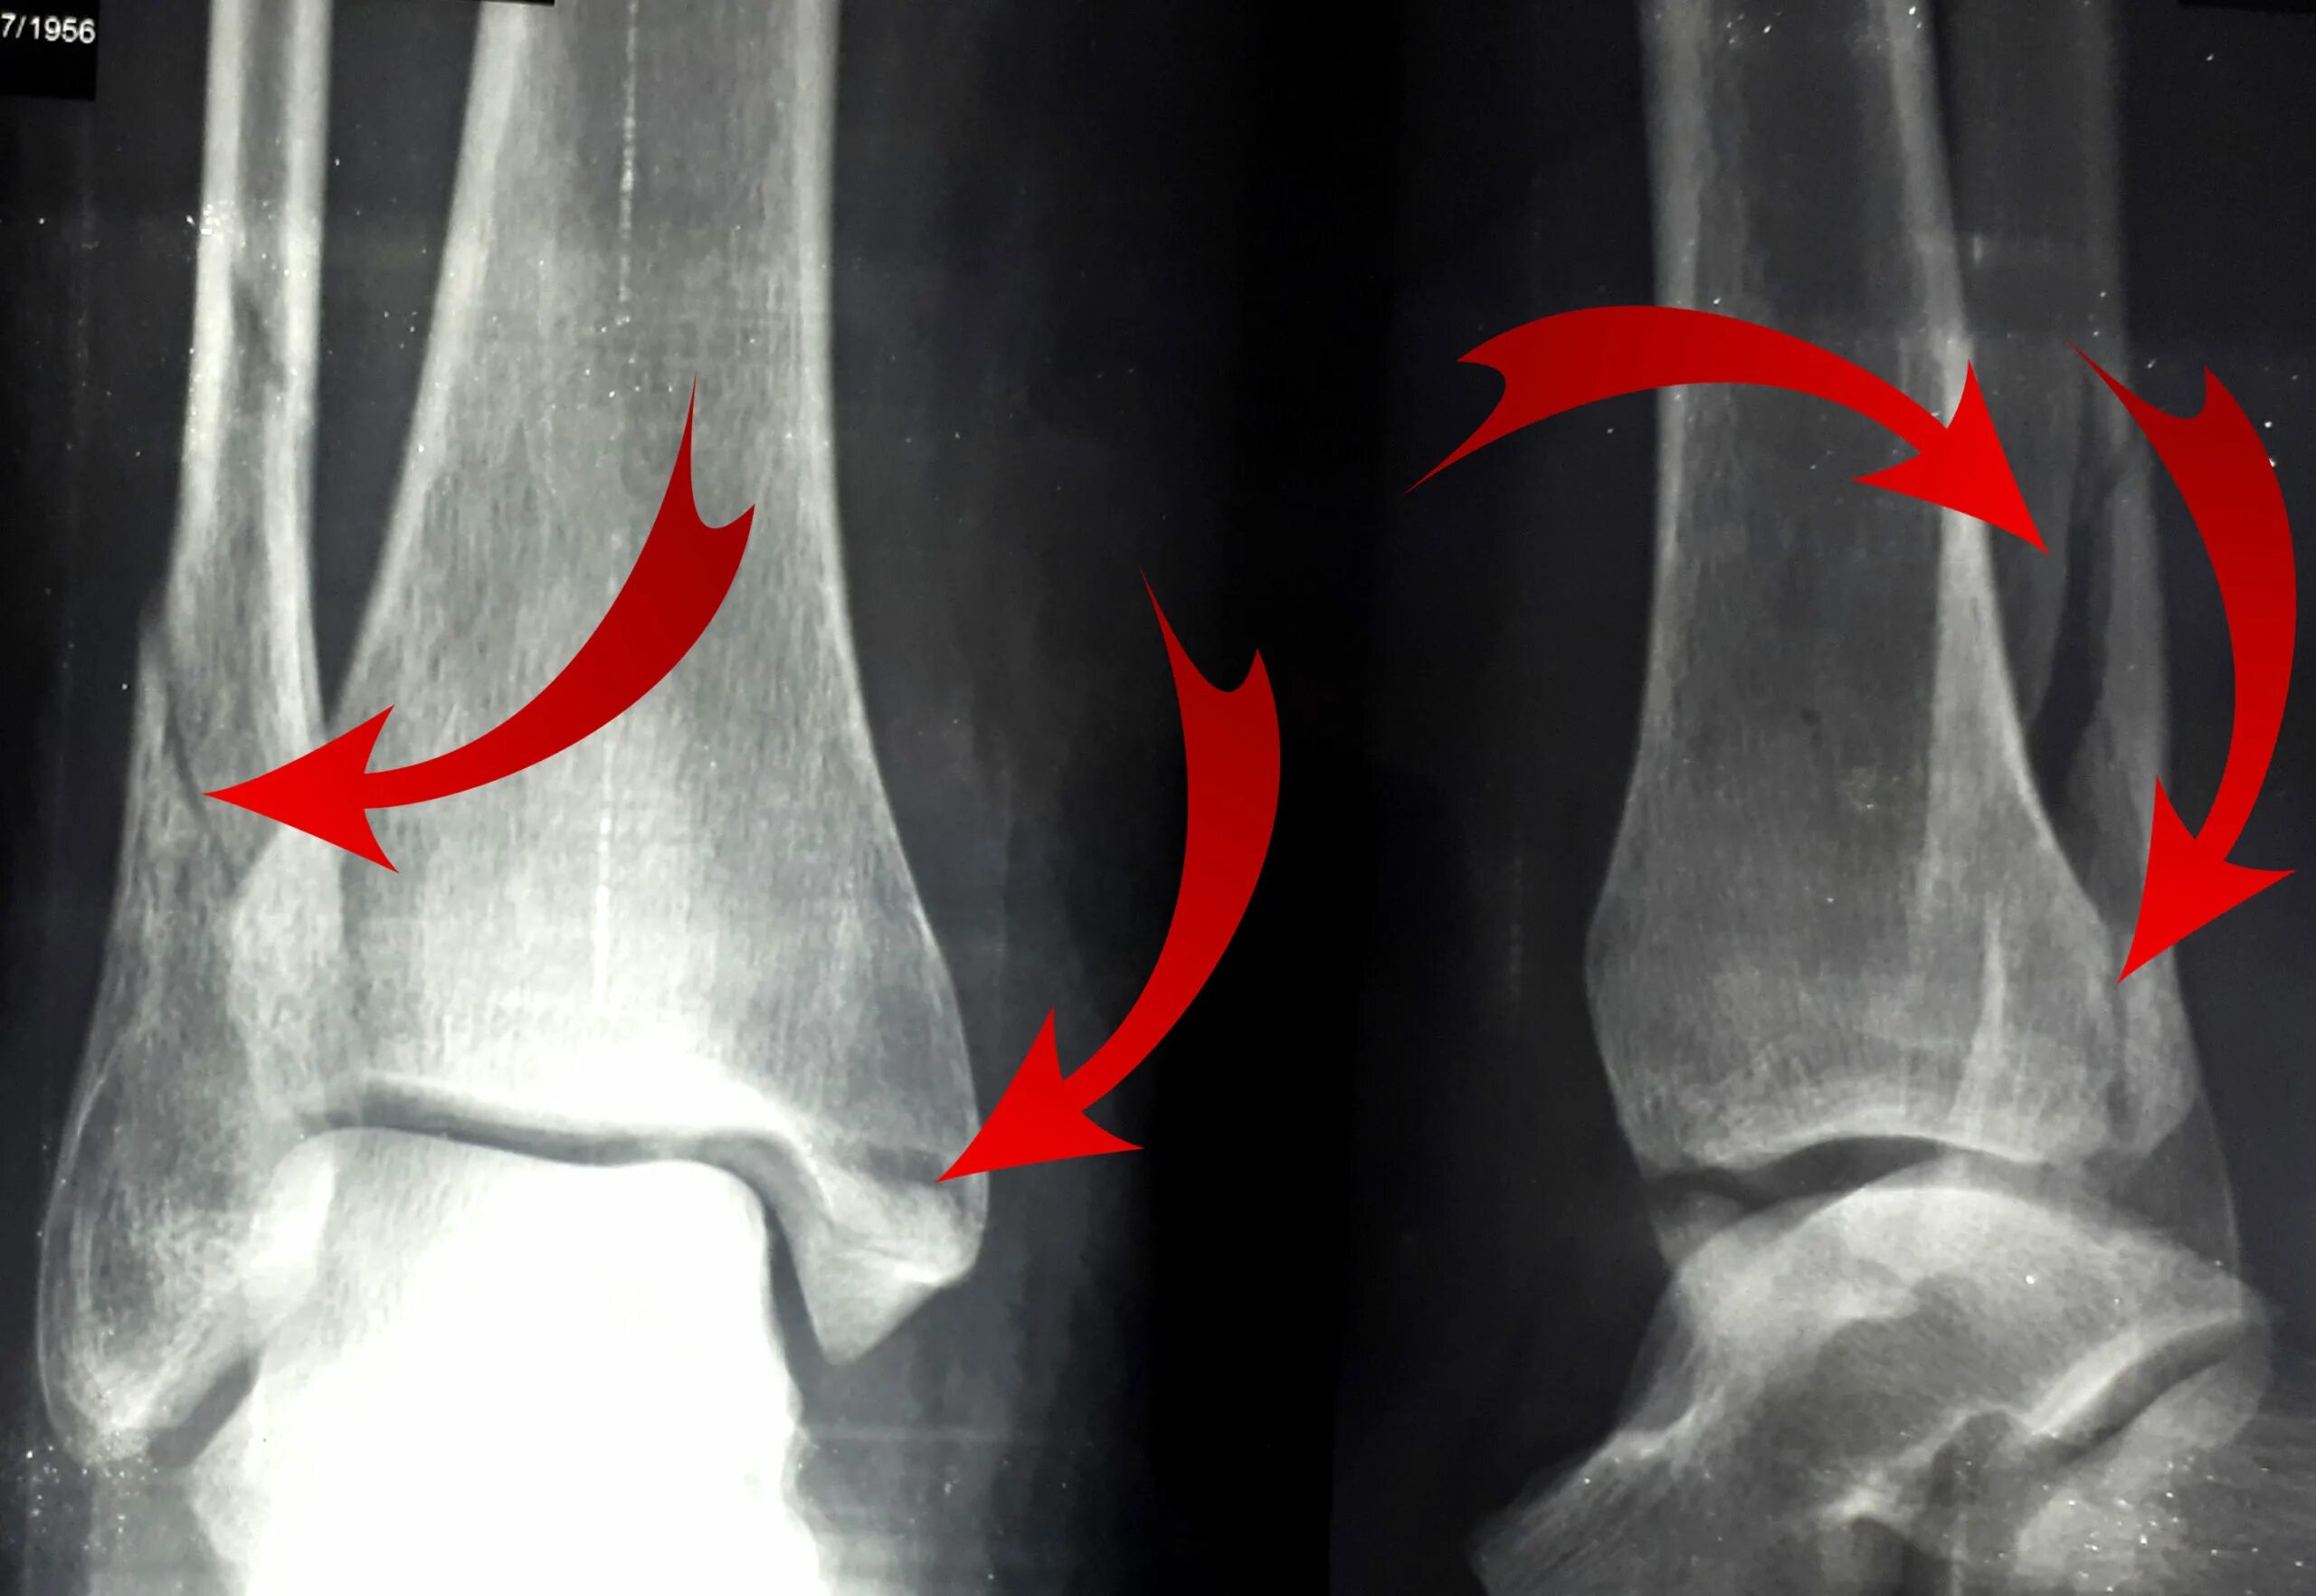

Наружная лодыжка голени